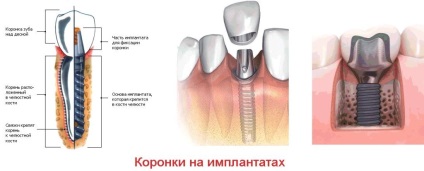

Crown implant

Coroanele pe implante pot fi fie din metal-ceramică și din ceramică. Ei au aceleași avantaje și dezavantaje ca tipurile convenționale cu fixare pe sol de pe dinte, dar prețul este crescut. Acest lucru se datorează creșterii complexității asigurării coroanei asupra procesului de implant.

Procesul de instalare este durata și apariția grave diferite, deoarece este necesar să se transfere o intervenție chirurgicală, PIN-ul de implantare și doar mai târziu a instala coroane.

coroane metalo-ceramice pe implante